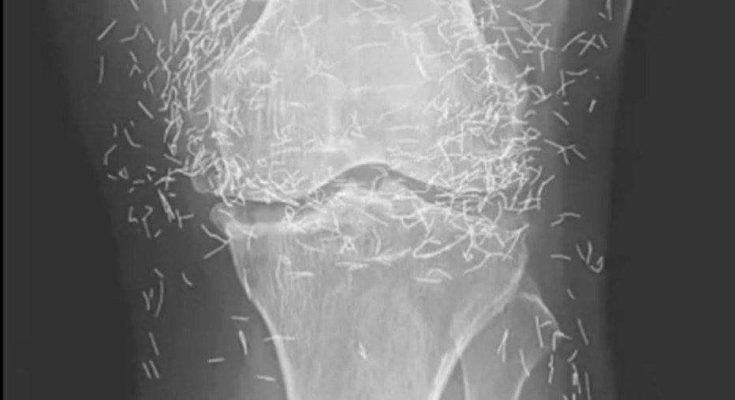

Years later, when doctors took X-rays to evaluate her knee condition, they weren’t prepared for what appeared on the images. Her knees were filled with dozens of bright, metallic flecks — tiny needles embedded deep within the joint area.

The findings were later documented in a case published by the New England Journal of Medicine.

Beyond inflammation, the needles created another problem: imaging complications. Metal objects can obscure parts of the anatomy on X-rays, making it harder for doctors to clearly assess joint damage or disease progression.

Even more concerning, the presence of metal inside the body can make certain scans dangerous. MRI machines rely on powerful magnetic fields, and embedded needles may shift during scanning, potentially damaging blood vessels or surrounding tissue. In short, future diagnostic options for this patient became limited.